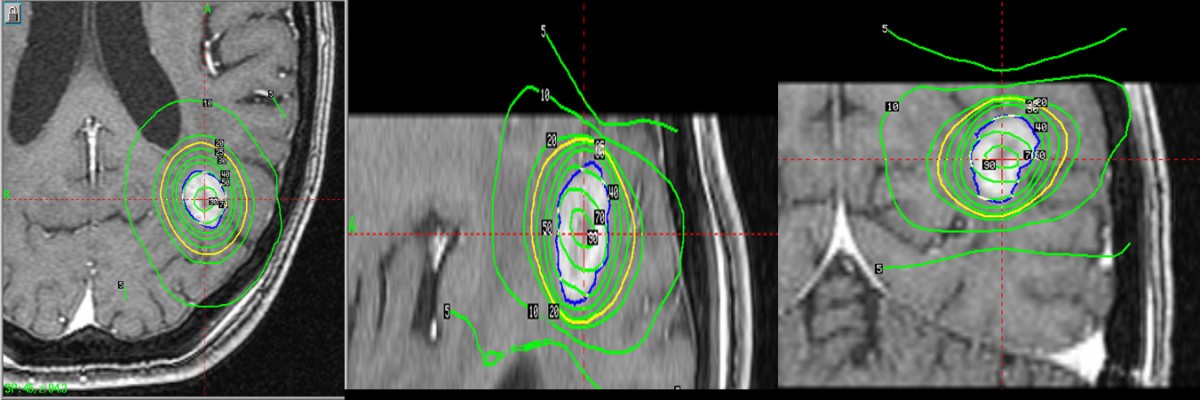

Represents the Tomotherapy dose distribution (in Gy) for one of the five presented patients.